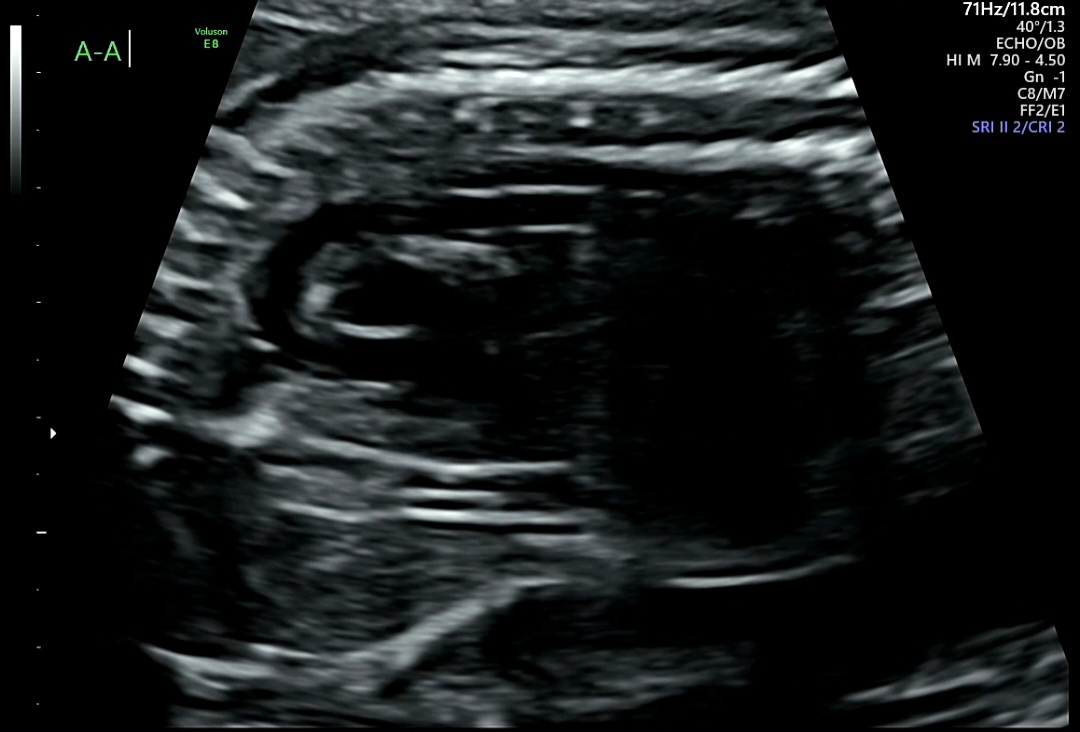

4) A-A (Aortic Arch, 대동맥궁)

A-A : 대동맥궁은 심장에서 나와 온몸으로 혈액을 보내는 중요한 통로

→ 활처럼 휘어지는 모습이 잘 보이면 정상적으로 형성된 것을 의미